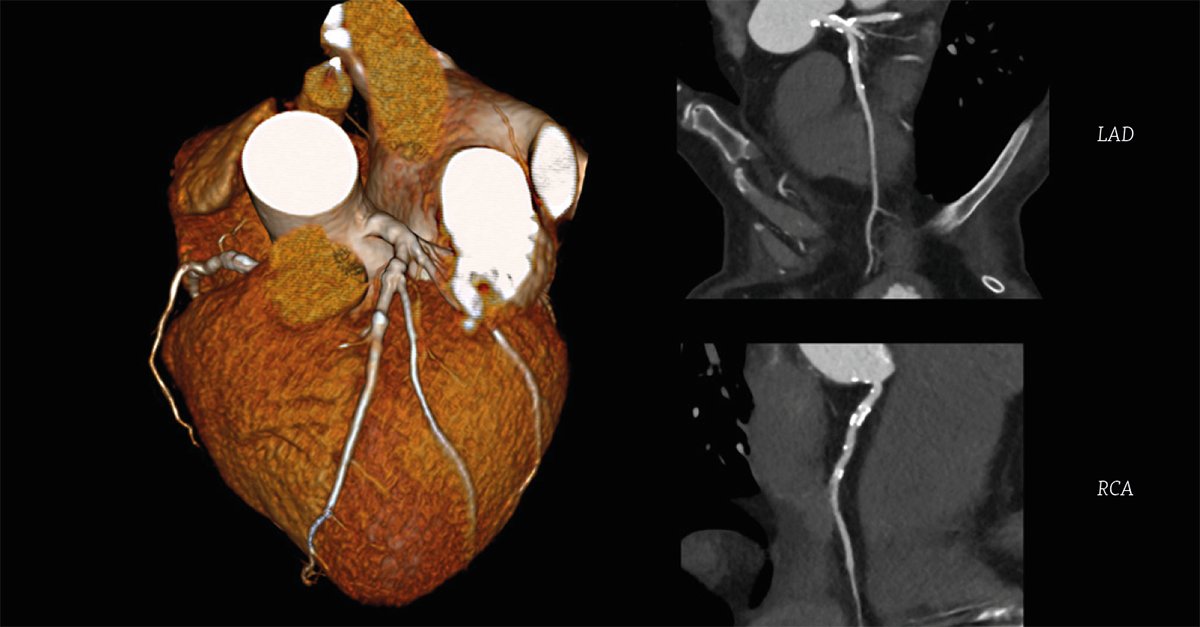

Congratulations I-MED Newtown on your new Aquilion ONE / PRISM #CT installation. The new system combines Canon's one-beat #cardiac and PIQE super resolution #deeplearningreconstruction to deliver sharp cardiac images. bit.ly/3IMDNlI

The new system combines Canon's one-beat #cardiac and PIQE super resolution #deeplearningreconstruction to deliver sharp cardiac images. bit.ly/3IMDNlI

Obtain greater diagnostic accuracy with the industry’s only super resolution #DeepLearningReconstruction technology for #cardiac #CT – Precise IQ Engine (PIQE), powered by Altivity. Visit the Canon team at #RANZCR2022 to hear more bit.ly/3vvLtBR

CanonMedicalANZ's tweet image. Obtain greater diagnostic accuracy with the industry’s only super resolution #DeepLearningReconstruction technology for #cardiac #CT – Precise IQ Engine (PIQE), powered by Altivity.

Visit the Canon team at #RANZCR2022 to hear more  bit.ly/3vvLtBR

Find out how the #DeepLearningReconstruction #AI technology on Canon Medical's Aquilion ONE / PRISM Edition has been a game changer for #lowdose #cardiac CTA examinations at the radiology department of Charité in Europe. Read the article. bit.ly/3bPIQk9

CanonMedicalANZ's tweet image. Find out how the #DeepLearningReconstruction #AI technology on Canon Medical's Aquilion ONE / PRISM Edition has been a game changer for #lowdose #cardiac CTA examinations at the radiology department of Charité in Europe. Read the article.